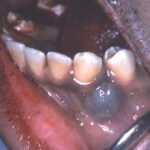

Oral mucosal melanoma= ميلانوم الاغشية المخاطية في الفم